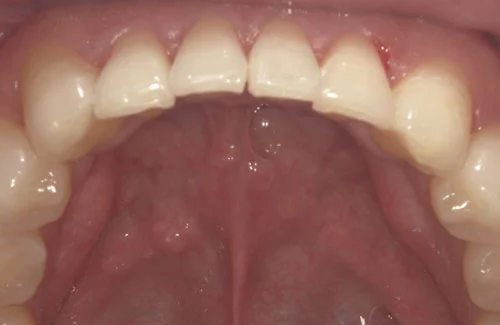

治療前後の写真

<症例2>歯が全体的にガタガタ、出っ歯でお悩み

歯列のアーチがやや狭く、それにより上下の前歯部にガタつきが生じている状態でした。

小臼歯部をわずかに広げてスペースを作ることで、お口元を整えつつガタつきを改善しています。

患者様と症状

主訴:全体的なガタガタ、出っ歯

性別・年齢:30代女性

問題点:上下前歯部の叢生(中程度)、ディープバイト

診断:前歯部の叢生を伴うアングルⅠ級の不正咬合

主なリスク:矯正中一時的に咬合しにくくなる、歯肉退縮

症状:叢生(そうせい) 過蓋咬合(かがいこうごう)

治療内容

治療期間:9ヶ月

治療費用:660,000円(税込)

プラン:26枚コース/モデレートプラン

抜歯:親知らずのみ抜歯

再診治療費:無し

追加治療費:無し

保定装置費:無し